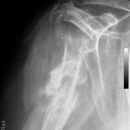

Subcapitale Fraktur und Tuberculum majus